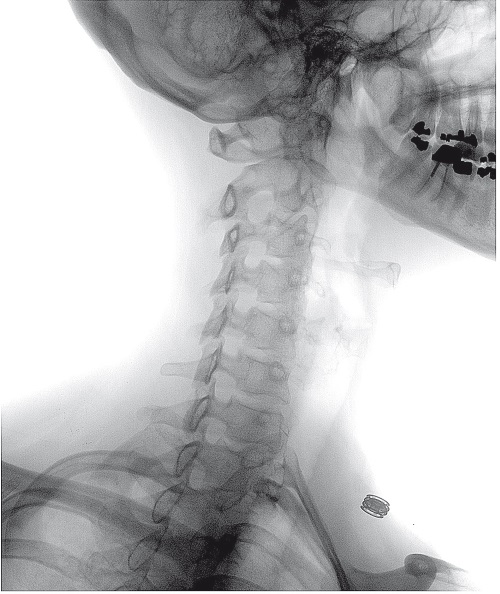

Наша проверка нетрадиционных методов лечения основана именно на принципах доказательной медицины, поэтому нам очень важно подробно объяснить, что это из себя представляет и как устроено. Мы не будем говорить о доказательной медицине в контексте современности, а вернемся в прошлое, чтобы посмотреть, как она возникла и развивалась, – тогда станет гораздо понятнее, в чем ее достоинства. В частности, мы увидим, как с помощью этого подхода удалось проверить действенность кровопускания – противоестественной, однако некогда весьма распространенной процедуры, при которой разрезали кожу и рассекали кровеносные сосуды. Считалось, что так можно исцелить от любого недуга.

Древнегреческие врачи не знали, что кровь циркулирует по организму, и полагали, что она может загнивать и тем самым вызывать недуги. Поэтому они настаивали на удалении застоявшейся крови и рекомендовали для каждой болезни свою процедуру. Например, заболевания печени требовали кровопускания из вены на правой руке, а недомогания, связанные с селезенкой, – из вены на левой.

Греческая медицинская традиция пользовалась таким авторитетом, что в последующие века кровопускание стало общепринятым методом лечения больных по всей Европе. В эпоху раннего Средневековья те, кто мог себе это позволить, обращались за кровопусканием к монахам, однако позже, в 1163 году, папа римский Александр III запретил монахам проводить эту жестокую медицинскую процедуру. С тех пор обязанность отворять кровь обычно исполняли местные цирюльники. К своей роли они относились весьма серьезно: тщательно шлифовали приемы и перенимали новые технологии. Помимо простого лезвия они применяли пружинный ланцет, позволявший сделать разрез заданной глубины. В дальнейшем их арсенал пополнил скарификатор, который имел несколько подпружиненных лезвий, рассекавших кожу одновременно.

У тех цирюльников, которые предпочитали менее технологичный и более естественный подход, была возможность использовать медицинских пиявок. В ротовом отверстии этих кровососущих червей-паразитов находятся три независимые челюсти, на каждой из которых около ста крошечных зубов. Пиявки служили идеальным средством для кровопускания из десен, губ или носа больного. Причем эти животные еще и вводят в ранку обезболивающие и сосудорасширяющие (усиливающие кровоток) вещества, а также антикоагулянты, препятствующие свертыванию крови. Чтобы выпустить у больного больше крови за один сеанс, врачи прибегали к бделлатомии – надрезали пиявке задний конец, чтобы всасываемая кровь из него вытекала. Тогда пиявка не могла насытиться и вынуждена была продолжать сосать.

Говорят, цилиндры с чередующимися красно-белыми полосами на современных вывесках парикмахерских символизируют, что цирюльники играли еще и роль хирургов, но на самом деле это связано с их кровопускательными обязанностями. Красный цвет олицетворяет кровь, белый – жгут, шарик на верхнем конце – медный сосуд для пиявок, а сам цилиндр – палку, которую больной сжимал в кулаке, чтобы кровь лучше шла.

В ночь на субботу состояние Вашингтона ухудшилось настолько, что рано утром он проснулся от удушья. Смотритель его владений, мистер Альбин Роулинз, сделал больному микстуру из патоки, уксуса и масла, но обнаружил, что тот едва в состоянии ее проглотить. Роулинз, имевший большой опыт кровопускания, посчитал, что необходимы решительные меры. Стремясь облегчить состояние своего хозяина, хирургическим ножом – ланцетом – он надрезал ему руку и выпустил в фарфоровую миску треть литра крови.

К утру 14 декабря не появилось никаких признаков улучшения, так что Марта Вашингтон вздохнула с облегчением, когда в поместье прибыли три врача и занялись лечением ее супруга. Доктора Джеймса Крейка, личного врача бывшего президента, сопровождали доктора Густавус Ричард Браун и Элиша Каллен Дик. Они верно поставили диагноз – cynanche trachealis (“круп” на латыни), что сейчас мы назвали бы воспалением и отеком надгортанника. Доступ воздуха в дыхательное горло Вашингтона был частично перекрыт, и потому ему было трудно дышать.

Доктор Крейк присыпал больному горло порошком из шпанской мушки, а когда это не помогло, решил отворить ему кровь – и выпустил еще пол-литра. В 11 часов утра процедуру повторили. Всего у человека около пяти литров крови, так что каждый раз Вашингтон терял значительный объем. Доктора Крейка, судя по всему, это не тревожило. Днем он выпустил больному еще целый литр крови.

Затем несколько часов казалось, будто кровопускание помогло: Вашингтону стало лучше, какое-то время он мог даже сидеть. Под вечер его состояние снова ухудшилось – и врачи в очередной раз провели кровопускание. Кровь оказалась вязкой и текла медленно. С современной точки зрения это говорит об обезвоживании, истощении запасов жидкости в организме в результате сильной кровопотери.

К ночи доктора могли лишь мрачно наблюдать, как их многочисленные кровопускания и всевозможные снадобья и припарки не вызывают ни малейших признаков выздоровления. Доктора Крейк и Дик впоследствии напишут: “Казалось, жизненные силы стремительно отступают под натиском болезни. К конечностям приложили пластыри, а на горло сделали горячий компресс из отрубей с уксусом”.

Джордж Вашингтон, великан ростом около 190 сантиметров, потерял меньше чем за день половину всей крови. Врачи, отвечавшие за его лечение, отстаивали необходимость столь решительных мер, видя в них последнюю надежду на спасение жизни больного, и большинство их коллег поддержали это решение. Однако в медицинском сообществе звучали и протесты. Хотя кровопускание уже много сотен лет считалось общепринятой медицинской процедурой, некоторые врачи, пусть и меньшинство, сомневались в его полезности. Более того, они утверждали, что кровопускание создает риск для больного независимо ни от части тела, из которой оно проводится, ни от удаляемого объема крови, будь то пол-литра или два. По мнению этих врачей, доктора Крейк, Браун и Дик, в сущности, убили бывшего президента, без нужды обескровив его.